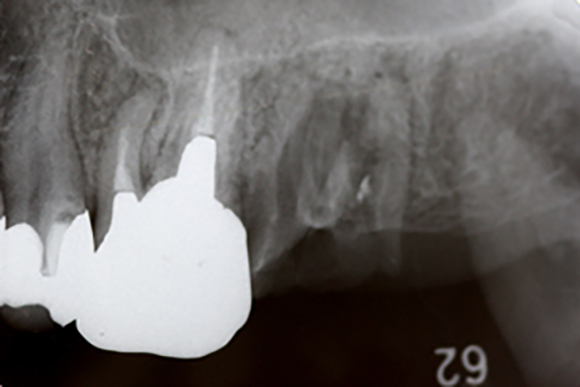

レントゲン写真

左上の一番後ろの奥歯がほとんどで虫歯で抜歯となりました。この部分に対してインプラントをしていくのですが、基本的に上顎には、下顎よりも長めのインプラントを埋入します。その際に上顎には上顎洞という空洞の部分があるのですが、ここには骨がありません。

抜歯後、上のレントゲンでは、右上の方に横に走る白い線が見えます。これが上顎洞の下底になります。そのため、ここに長めのインプラントを埋入すると上顎洞に触れる恐れがありますので、上顎洞の所にインプラントの埋入と同時に骨をつくるのが上顎洞挙上術です。

そこに対して、細い専用の道具でインプラントの入る通路を形成していきます。次のその先端部分から人工の骨を入れて行きます。

上のレントゲンの太い棒の先の部分に上顎洞の下底を貫通して白く顆粒上の物が写っているのが見えます。これが、人工骨を入れた部分になります。この分、インプラントが入るスペースが出来たので、ここに埋入していきます。

こののち6ヶ月ほど骨の成熟とインプラントと骨の結合を待ち、上の被せものを作って行きます。

今回使用したインプラントは、3iの新型インプラントのプリベールというもので、できるだけ周囲の骨が減少しにくくなるように設計されているインプラントです。